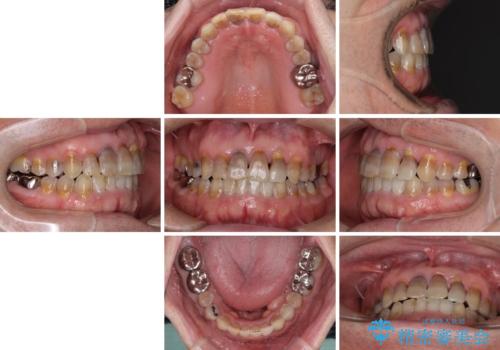

上顎の狭窄歯列 インビザラインによる拡大矯正

- 前歯の叢生と臼歯のクロスバイトを気にして来院された患者様です。

急速拡大装置による上顎の側方拡大を行い、その後はインビザラインより歯列を改善することとしました。

20代後半以降の男性は上顎骨の側方拡大処置の成功率が低く、今回も骨を拡大することができませんでした。

しかしながら、歯列を側方に拡大することができ、その後はインビザラインにて叢生を解消することができました。